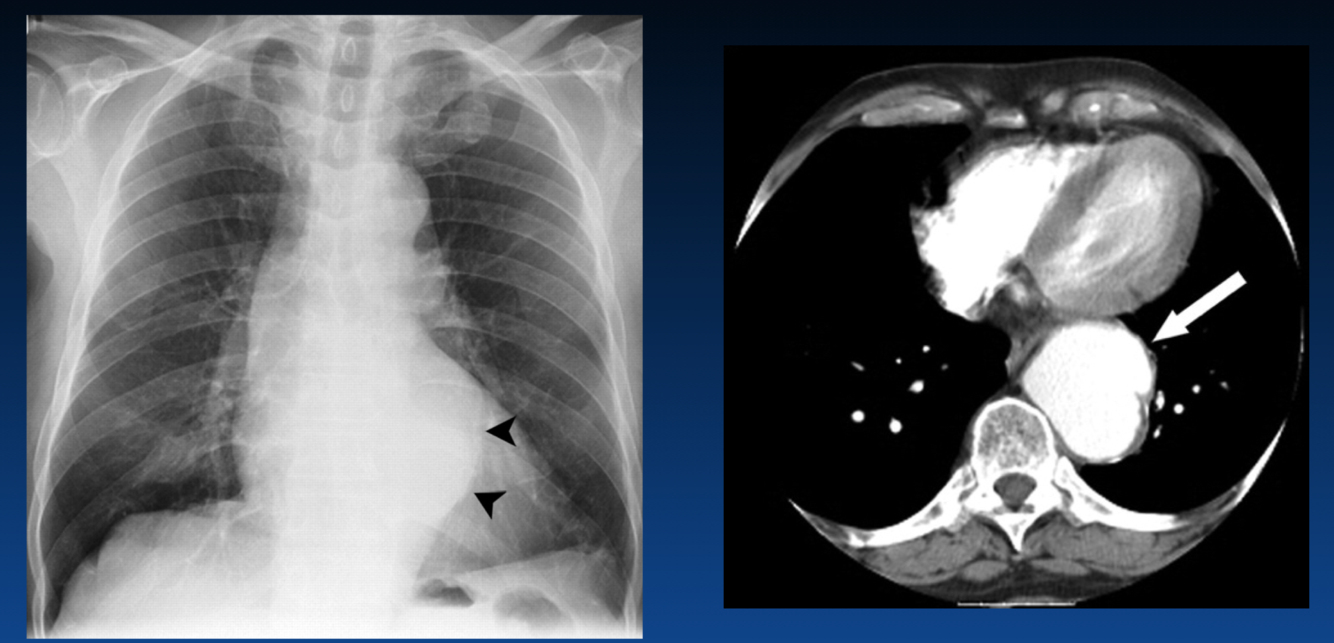

The left atrium is enlarged. What sign is the arrow pointing that indicates this?